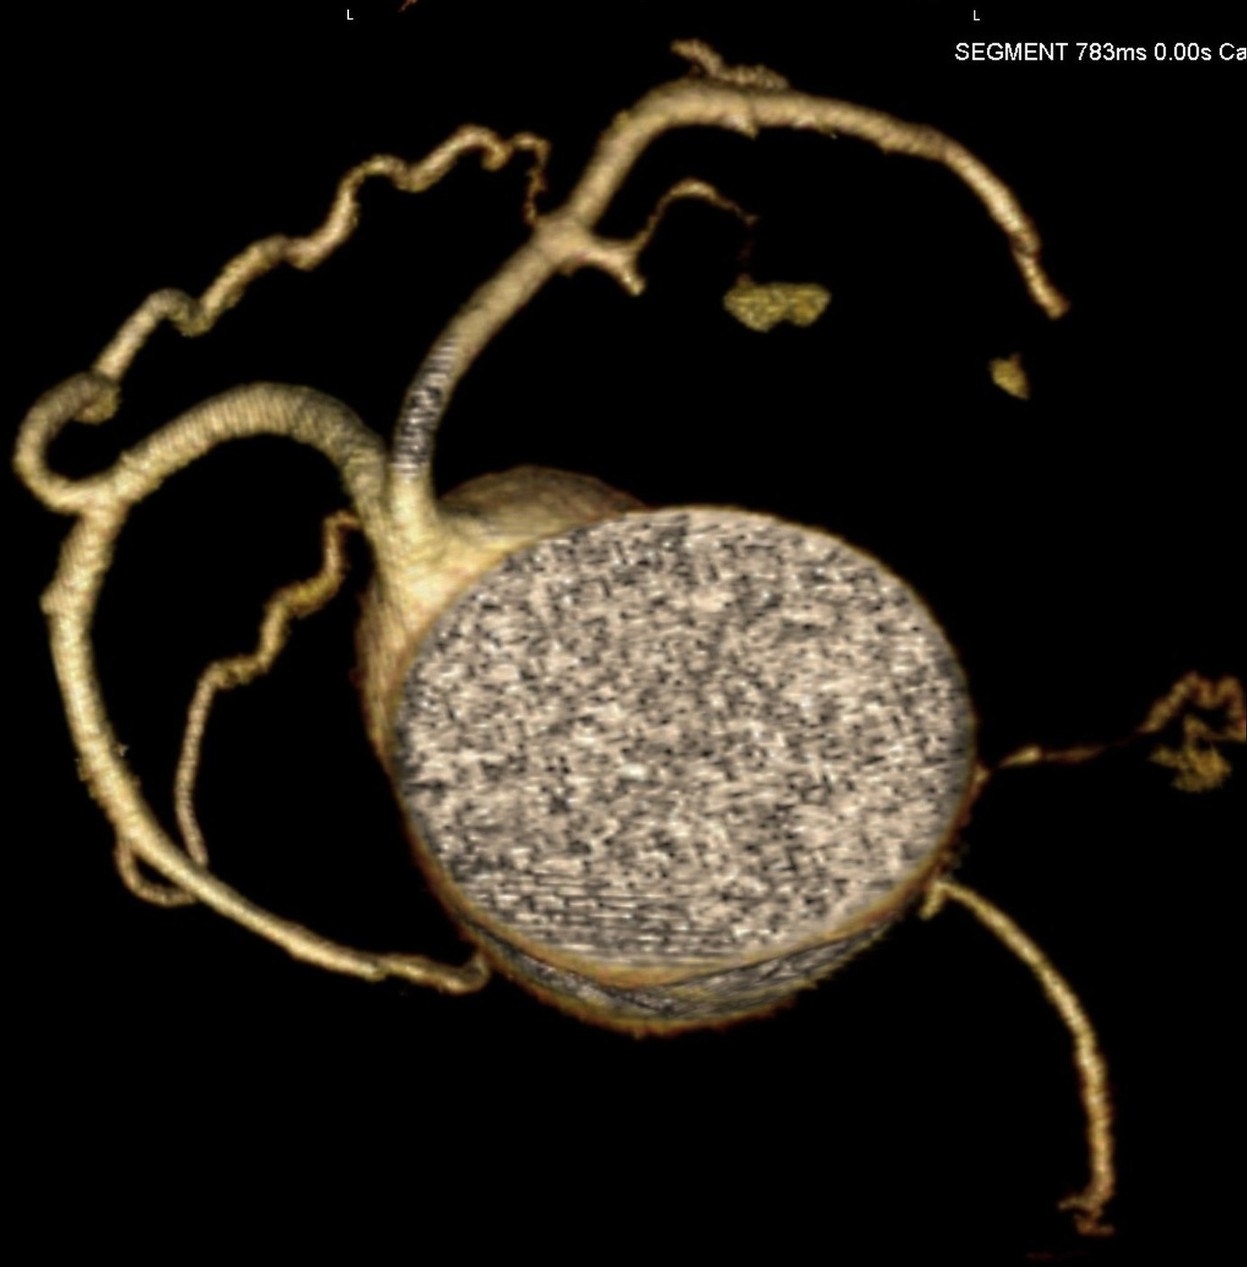

标题: CT24400:患者54岁,心前区不适进行心脏冠脉造影检查。 [打印本页]

标题: CT24400:患者54岁,心前区不适进行心脏冠脉造影检查。

患者54岁,心前区不适进行心脏冠脉造影检查。高手看看有问题没有?

图像很漂亮,好像未见异常